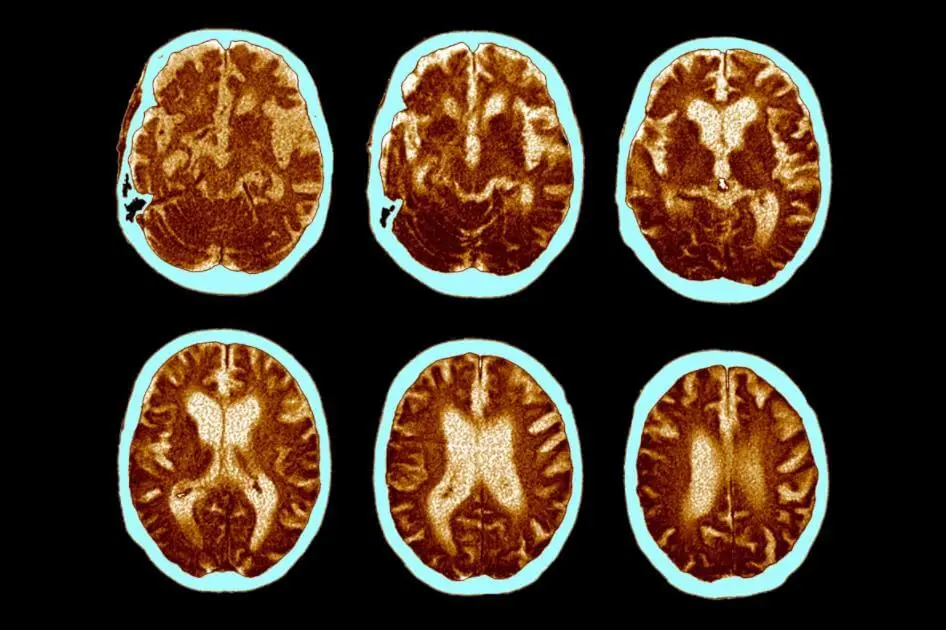

How dementia develops

Above:A 68-year-old woman with a 10-year history of cognitive impairment showed marked hypometabolism with a pattern suggestive of Alzheimer's disease prior to PET scan, PET scan after treatment with inhibitor (RI). Gradually approaching the normal brain, the patient's cognitive ability improved significantly.